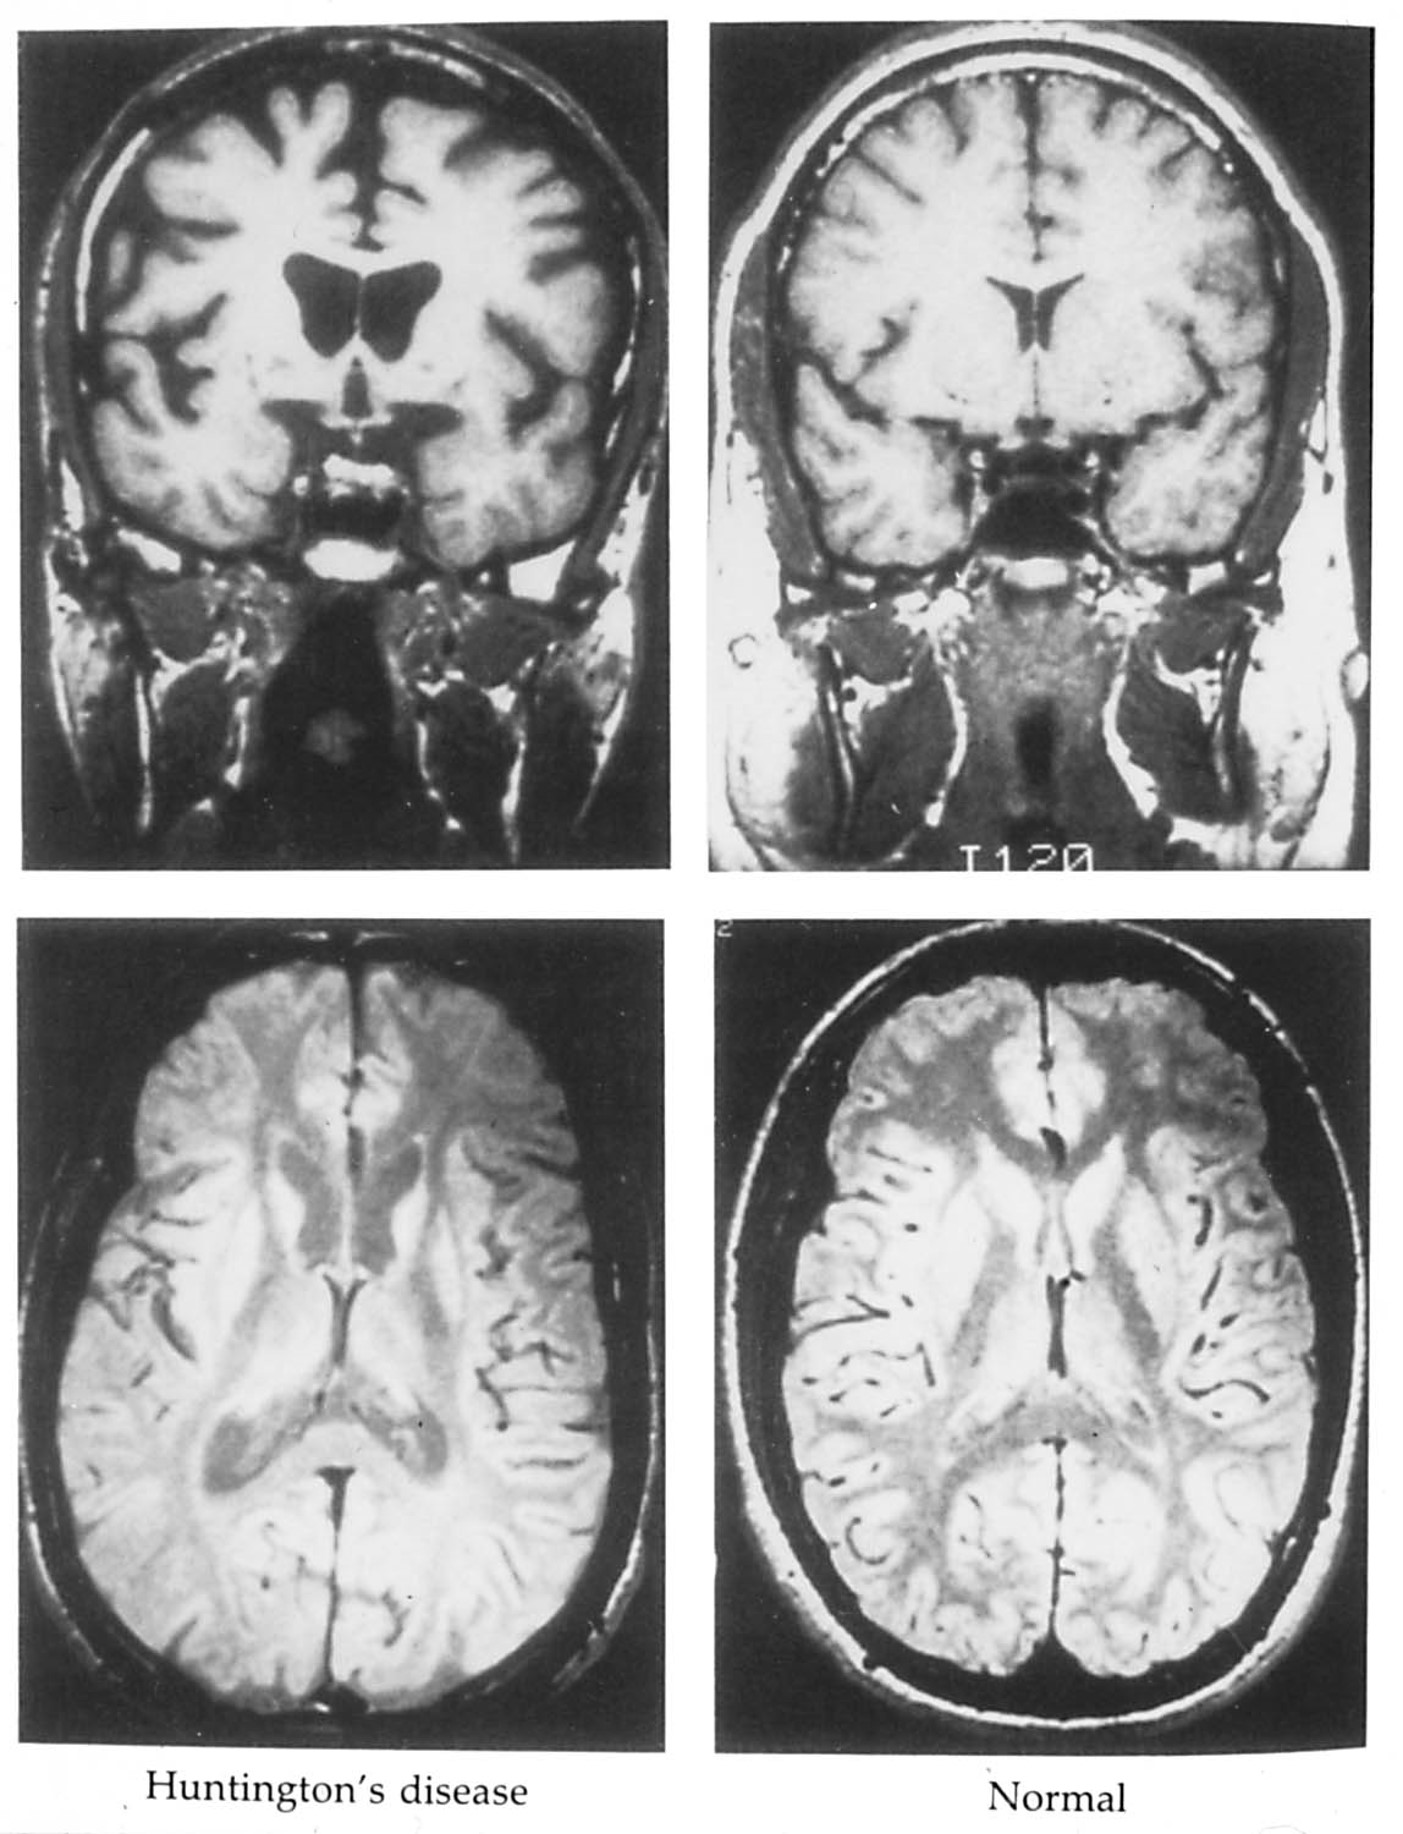

huntington’s chorea is a hyperkinetic disorder

Images of the brain from a patient with Huntington’s disease reveals enlarged ventricles and shrunken caudate and putamen nuclei bilaterally.

According to the DeLong model, neuronal loss in the caudate is due primarily to the loss of neurons that use enkephalin co-localized with GABA.